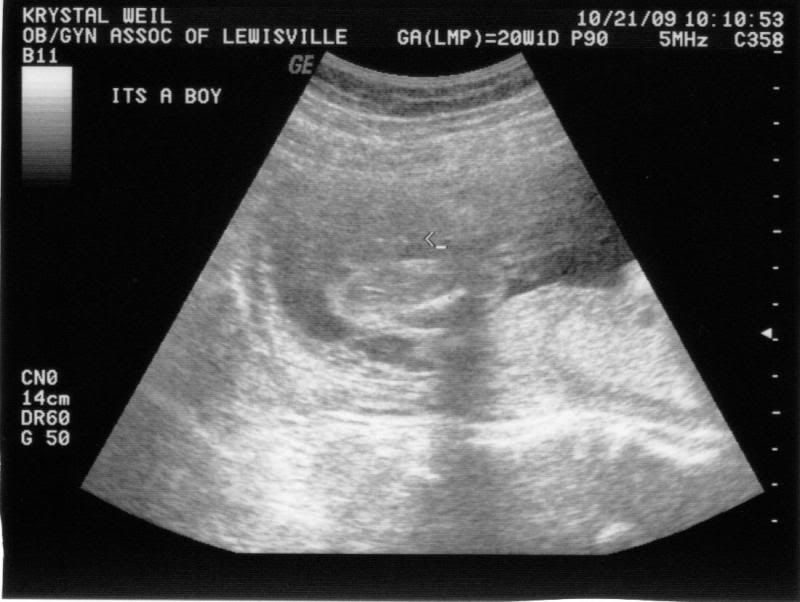

Well without drawing it out, we are having a boy! We are both so happy and can't wait to meet him. He was so cute! We got to see facial features. His face isn't completely done, but we could see where his eyes, nose and lips will be. His sweet balled up fists were moving and we saw his heart beating. It's the most precious thing I have ever seen. Life is so beautiful and God is SO good!

Here is a couple pictures from the ultrasound today. Enjoy!

It's a boy....